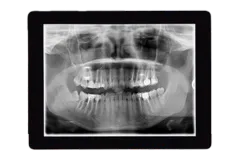

Digital X-Rays

Our practice utilizes digital X-rays to obtain clear, high-resolution images of your teeth, jaw, and surrounding structures. Digital X-rays offer numerous advantages over conventional film X-rays. They emit significantly less radiation, making them a safer option for patients, especially children. With enhanced image quality, the crystal-clear images allow for better detection of dental issues, enabling more accurate diagnoses. Digital X-ray images are available instantly, allowing for faster diagnosis and orthodontic treatment planning. Furthermore, digital X-rays eliminate the need for chemical processing, making them a more eco-friendly choice.